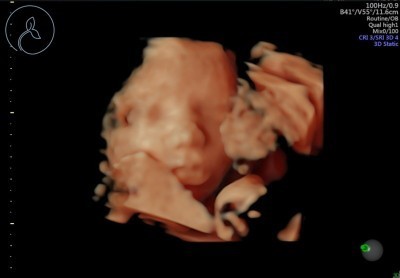

อยากเห็นหน้าใจจะขาดแล้วค่ะ🥰 #ลูกสาวทีมกันยา